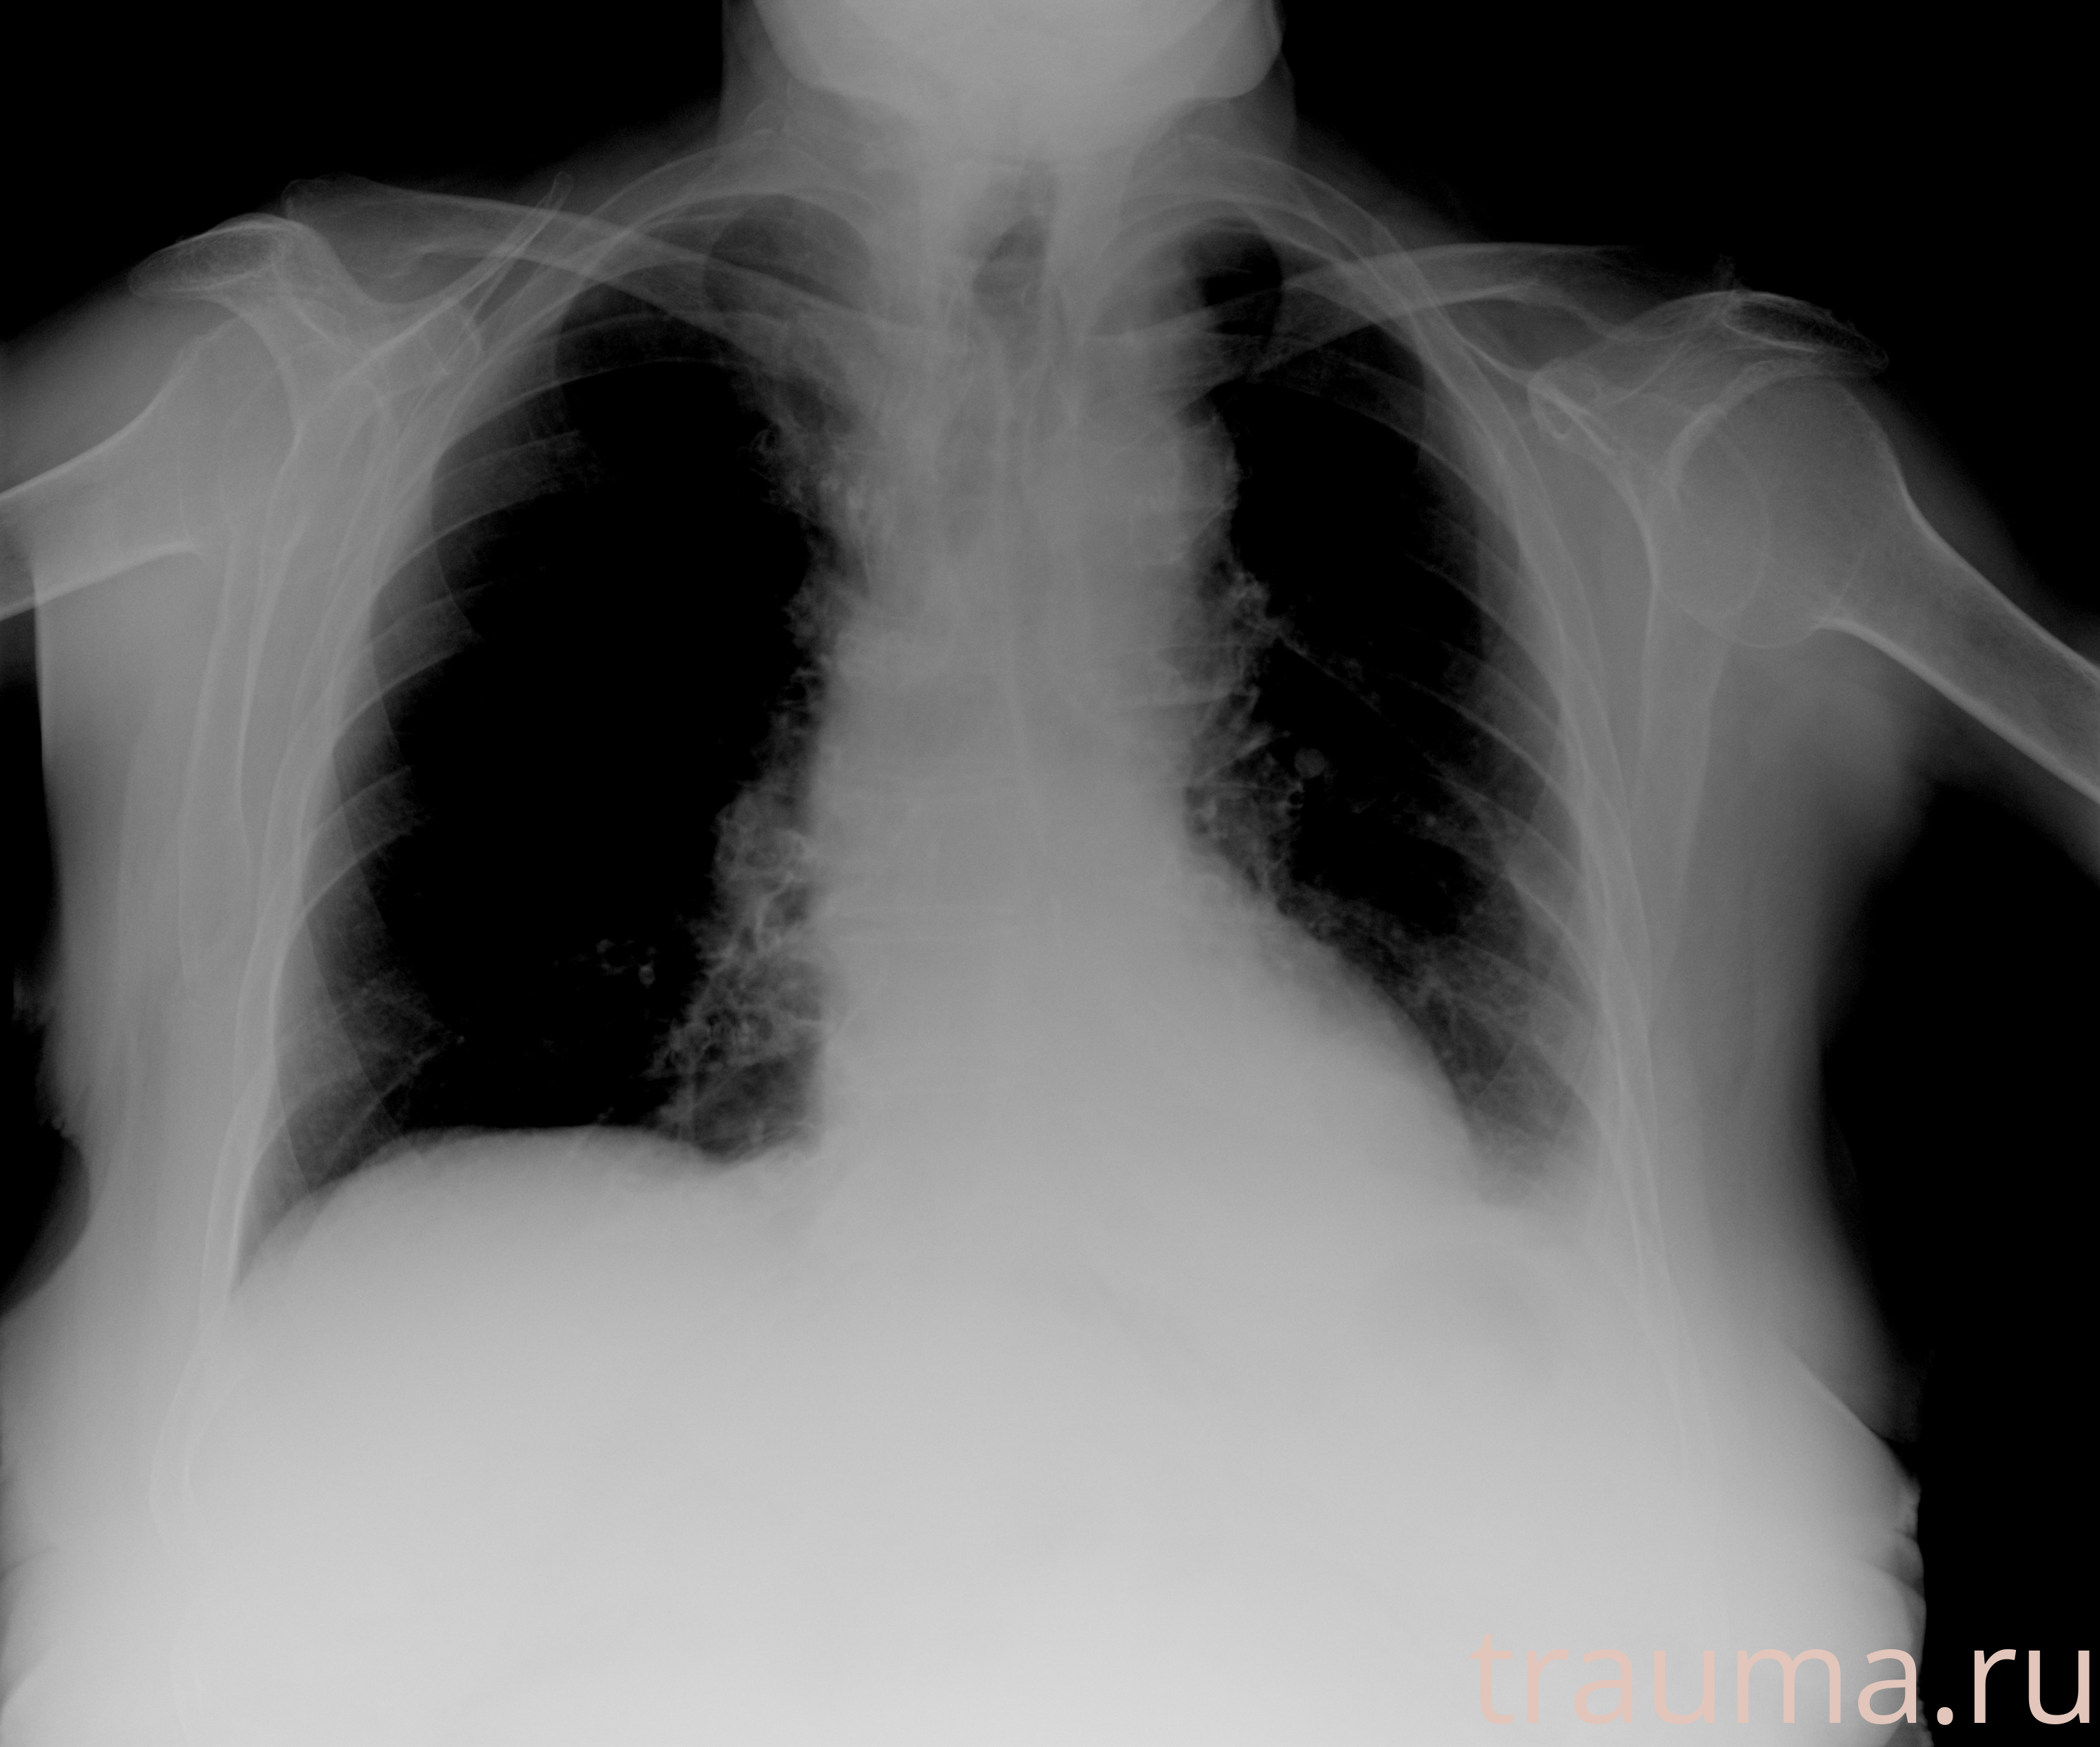

Рентгенограммы

Рентген на дому: по вашему адресу приезжает врач-рентгенолог, травматолог-ортопед с мобильным рентгеновским аппаратом, проводит диагностику травмы или заболевания, делает необходимые рентгенограммы, дает рекомендации по дальнейшему лечению. Получить качественные снимки в домашних условиях возможно благодаря уникальной методике, разработанной МосРентген Центром для института  Склифосовского

Яркость: 1   Контраст: 1   Инвертировать: 0 Увеличение: 1

Перетаскивайте мышь вверх/вниз для контраста, влево/право для яркости. Прокрутка колесом изменяет масштаб. Нажмите Сбросить для возврата к исходному изображению. При увеличении держите мышь в той области, которую хотите рассмотреть.